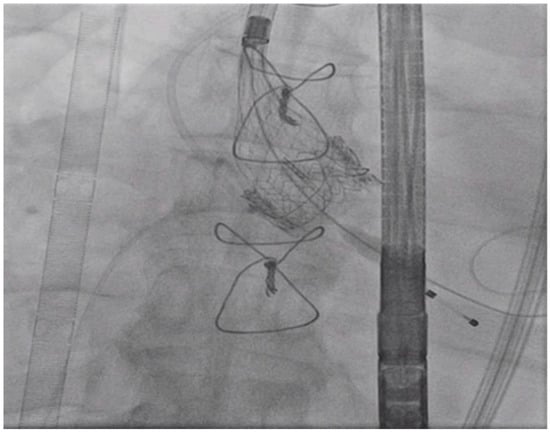

Tandem Life® support was increased to 4 L per minute. At this point, the Gore dry seal sheath was removed from the right femoral artery, and the 26 mm Medtronic CoreValve EvolutR valve delivery system was introduced via the right femoral artery via its in-line sheath, advanced into position across the valves as shown in Figure 4, and deployed in standard fashion with right ventricular pacing at 100 beats per minute.

Figure 4.

Left Anterior Oblique (LAO) Caudal View: Valve being deployed while transvenous pacemaker in place.

The CoreValve position was confirmed by TEE and fluoroscopy before its deployment. The rotational fluoroscopic view of is shown in Figure 5. TEE and aortogram showed a well-seated transcatheter aortic valve with trace perivalvular leak and good positioning of the prosthesis.

Figure 5.

Left Anterior Oblique (LAO) view: Valve is deployed.